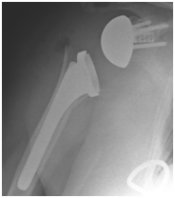

Stemmed shoulder replacement

X-ray of shoulder demonstrating a stemmed shoulder replacement